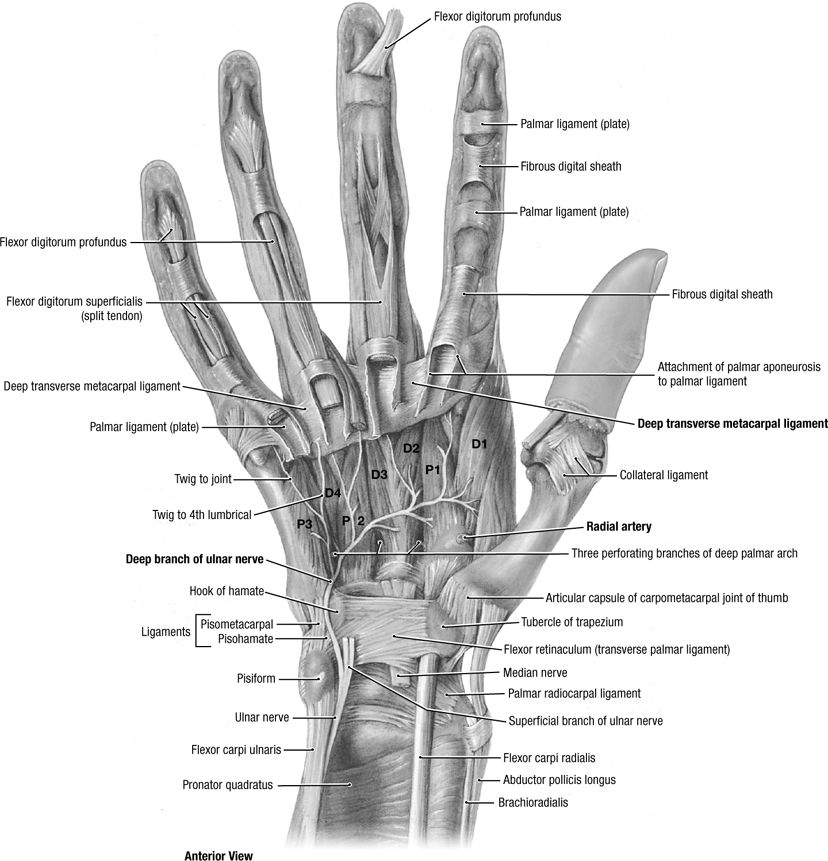

Hand

Routine

This includes an off axis view of the wrist but should

not be used to assess wrist alignment. Good overview for hand pain. May

need additional wrist views if pain is proximal or difficult to

localize. Important to have fingers spread on lateral view so that all

volar plates are well visualized. MRI or US may be useful adjuncts to

look at adjacent soft tissues.

![]() |

|

Figure 3 (A) PA of hand. (B) Oblique of hand. (C) Lateral of hand.